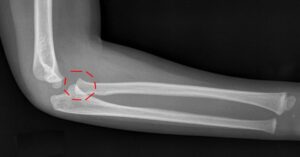

Dirsek çıkığı, dirsek ekleminde kemiklerin normal pozisyonundan kayması sonucu oluşur. Bu durum ciddi bir yaralanmadır. Dirsek çıkığı, genellikle travmalar sonucu meydana gelir. Bu durum genellikle düşme, spor yaralanmaları veya trafik kazaları sonucunda oluşur. Ani travmalar da dirsek çıkığına yol açabilir. Dirsek Çıkığı Tedavisi zamanında yapılmadığında sinir ve damar hasarına yol açabilir.

Dirsek çıkığı, dirsek ekleminde kemiklerin normal pozisyonundan kaymasıyla oluşur. Bu durum ciddi bir yaralanmadır. Genellikle bu durum düşme, spor kazaları veya trafik kazaları sonucu meydana gelir. Ani travmalar da dirsek çıkığına yol açabilir. Bu tür yaralanmalar ciddi komplikasyonlara yol açabileceği için doğru tedavi büyük önem taşır. Dirsek çıkığı tedavisi, her yaş grubundan ve farklı sağlık durumlarından bireyler için uygulanabilir.